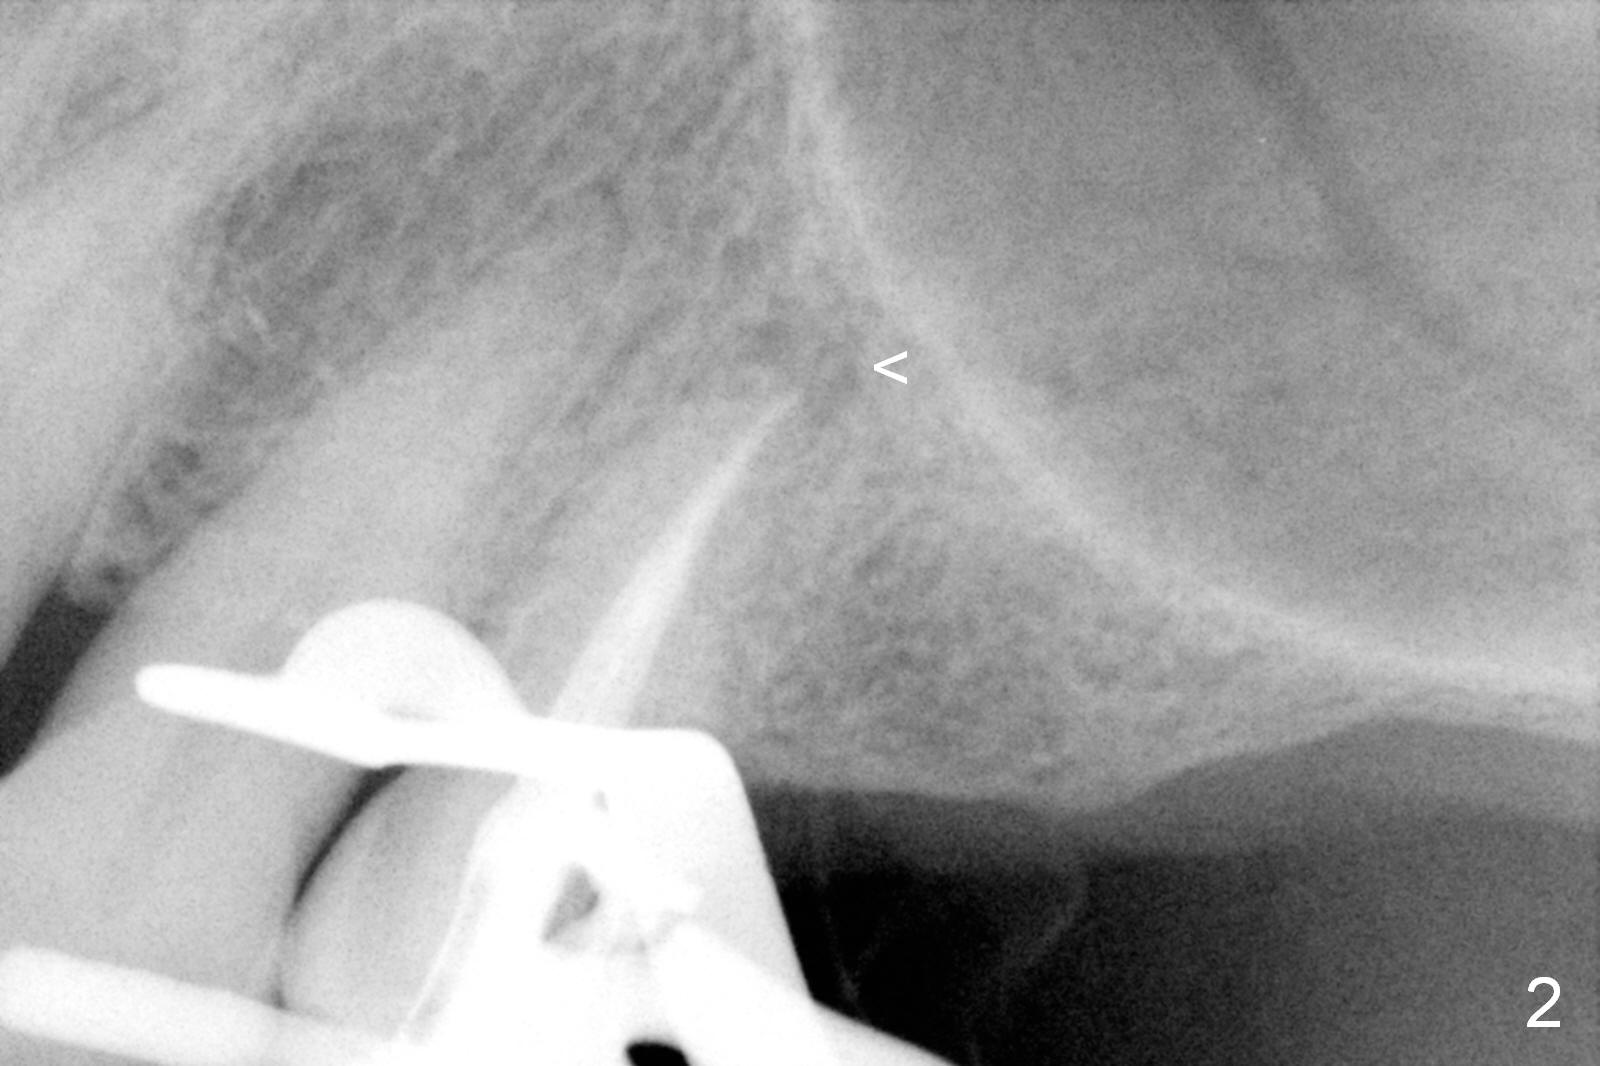

A 64-year-old man (MM) had caries at the tooth #12 (Fig.1), requiring root canal therapy (RCT, Fig.2). One year later, the periapical radiolucency reduces (Fig.3 <, as compared to that in Fig.2). The tooth remains asymptomatic 7 years posts RCT (Fig.4). A year later, the tooth has pain and buccal gingival swelling (probing tenderness); periradicular radiolucency is evident (Fig.5 arrowheads). It appears that the root fractures. Between the 7th and 8th years post RCT, the patient masticated mainly on the left side, while implants were placed at #30 and 31. The patient plans to have 4 implants in the upper left sextant (Fig.6). While implants are being placed at the site of #12 (Clindamycin) and 13, sinus lift seems mandatory at the sites of #13 and (initial depth will be 5-6 mm). By the time implants to be placed at #14 and #15, the bone height may increase.